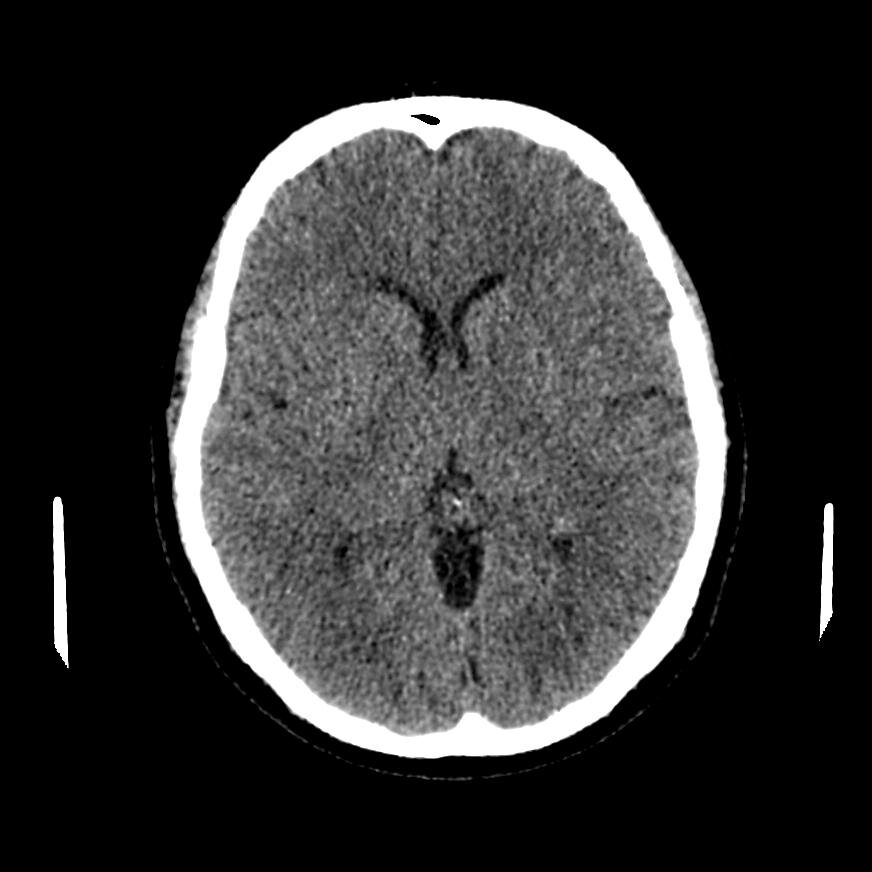

КТ головного мозга